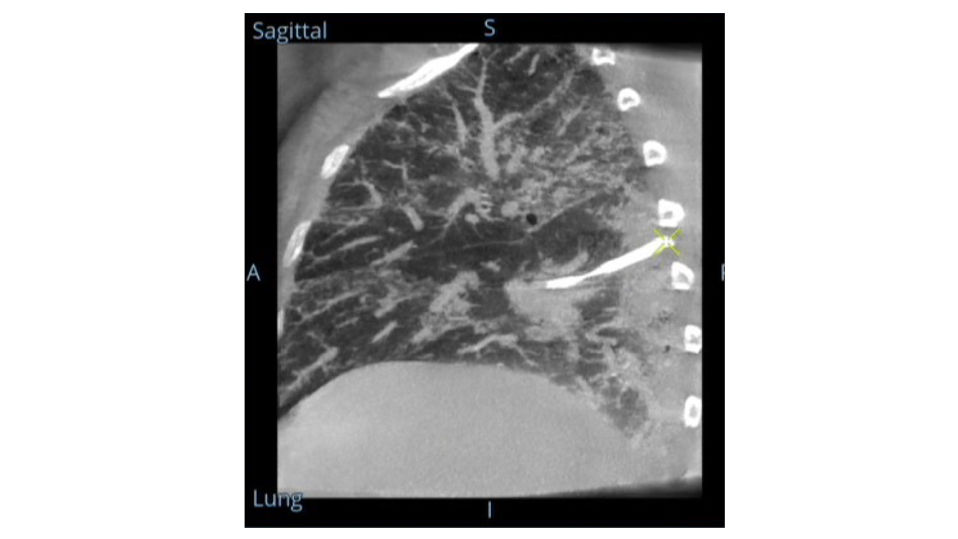

Analysieren Sie Ihre Scans mit dem GE Volume Viewer – genauso intuitiv wie am CT. Profitieren Sie von der vollständigen Darstellung axialer, koronarer und sagittaler Ebenen sowie von MIP-Ansichten und 3D-Visualisierungen im VR-Modus. Scrollen Sie durch bis zu 512 Schichten mit nahtloser Anpassung der Schichtdicke – für eine präzise Befundung direkt im OP.